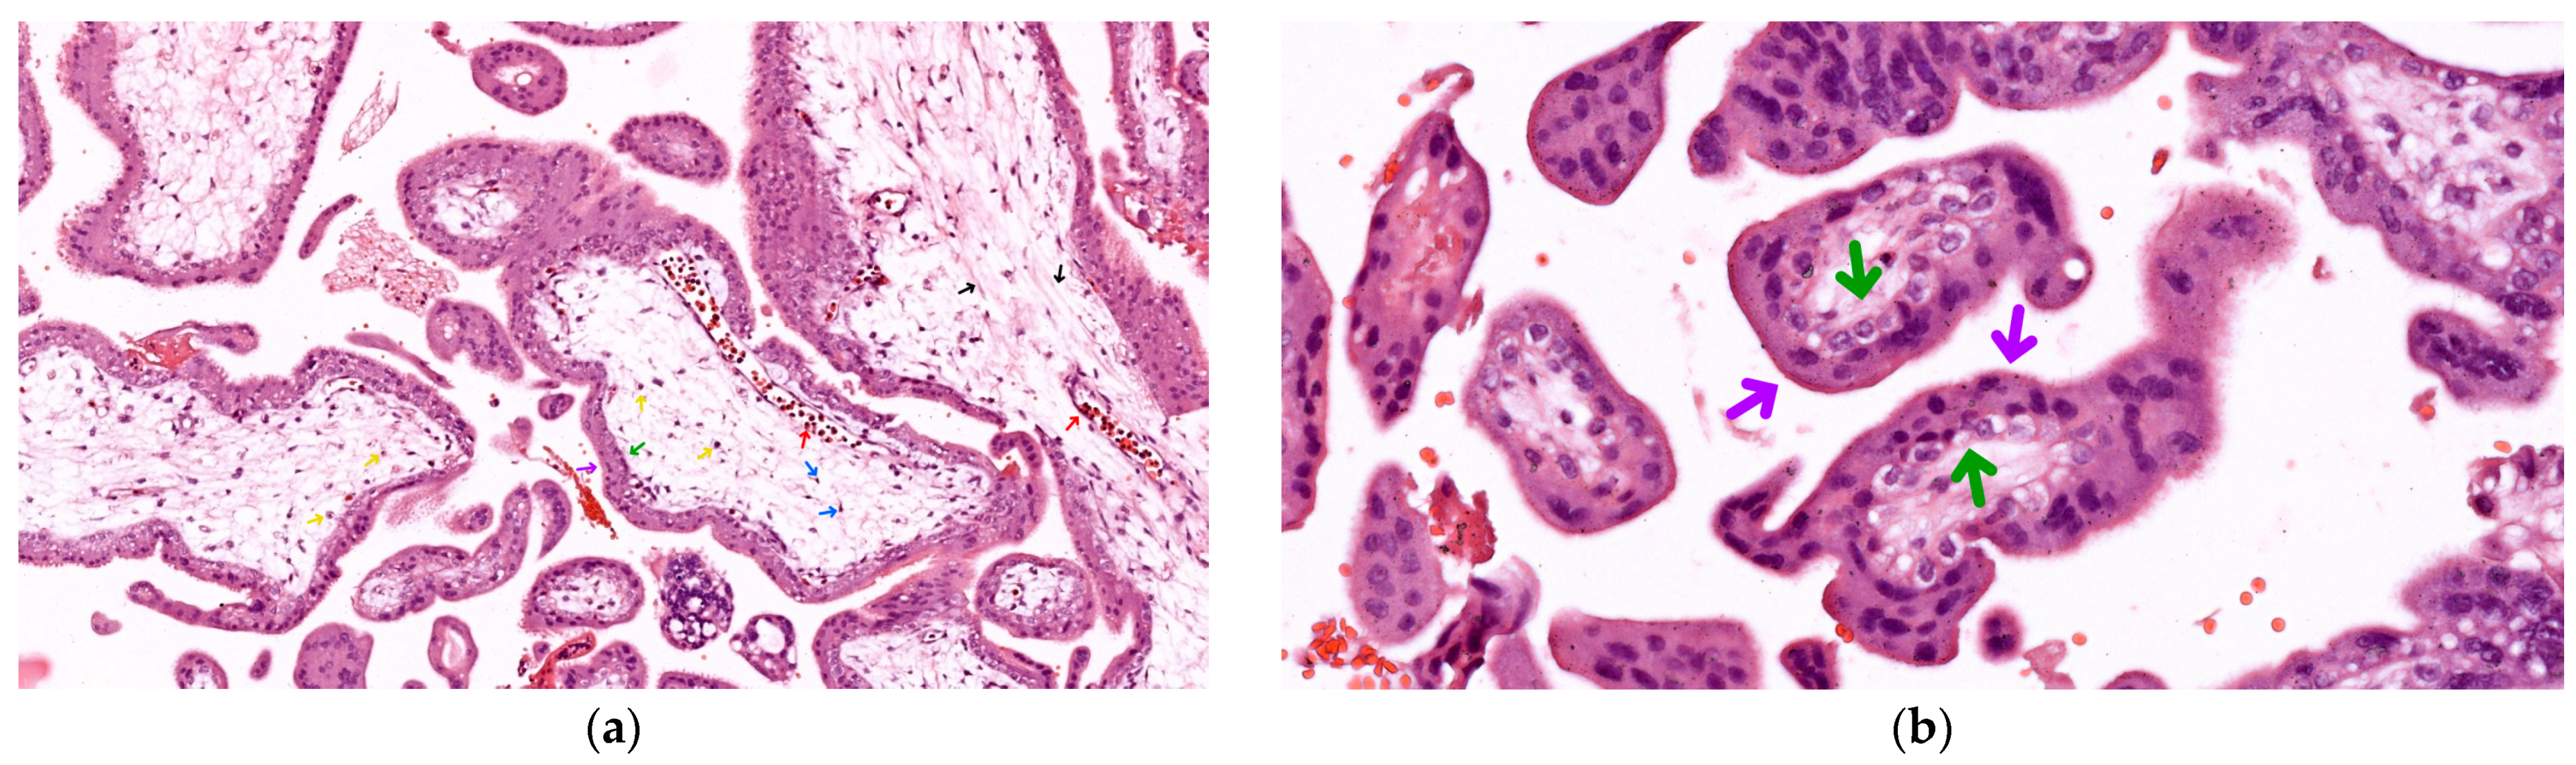

As seen in Figure 1a, in these first-term fetal placenta samples, we identified mostly mesenchymal villi with a diffuse stromal axis centrally containing thin collagen and reticulin fibers (black arrows), fibroblasts (blue arrows), scarce Hofbauer macrophages (yellow arrows), and rare fetal vascular elements (red arrows) encased within a trophoblastic epithelium peripherally.

As seen in Figure 1b, the trophoblastic epithelium covering the villi is comprised of two distinct layers:

• Syncytiotrophoblast (purple arrows): The outer layer, consisting of a continuous cytoplasmic mass with multiple nuclei arranged in a single row. This layer also contains numerous lipid vacuoles and is in direct contact with maternal blood;

• Cytotrophoblast (green arrows): An inner layer of cuboidal cells with clear cytoplasm and large euchromatic nuclei. This layer is prominent only until the fourth month of gestation, after which it becomes less distinct.

This complex histological structure allows the placenta to perform its vital functions throughout pregnancy, facilitating fetal growth and development while maintaining the physiological separation of maternal and fetal circulations.